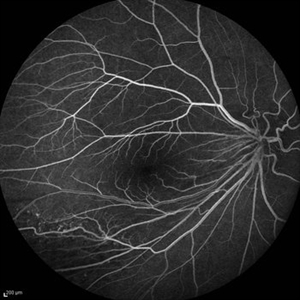

Behcet's Disease Behcet's DiseaseMar 13 2013 by Hamid Ahmadieh, MD Early phase FA of the right eye of a 23-year-old man with retinal vasculitis and branch retinal vein occlusion (BRVO) due to Behcet's disease . Photographer: Solmaz Shahmohammad, Negah Eye Center, Tehran Imaging device: Heidelberg Spectralis Condition/keywords: branch retinal vein occlusion (BRVO), retinal vasculitis